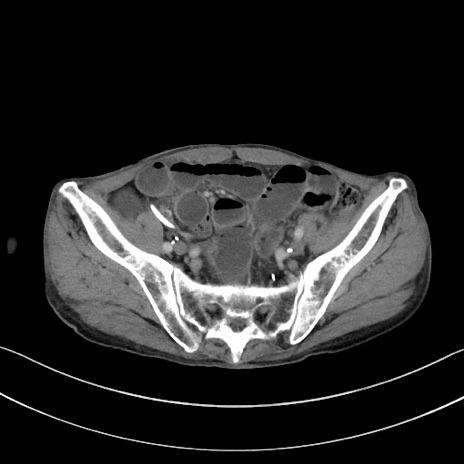

症例3(横断像)

【症例】 70歳代男性

【主訴】右鼠径部腫瘤、疼痛

【現病歴】本日朝より上記主訴あり、受診。

【既往歴】膀胱癌にて膀胱全摘、両側尿管皮膚瘻

【データ】WBC 5600、CRP 0.56